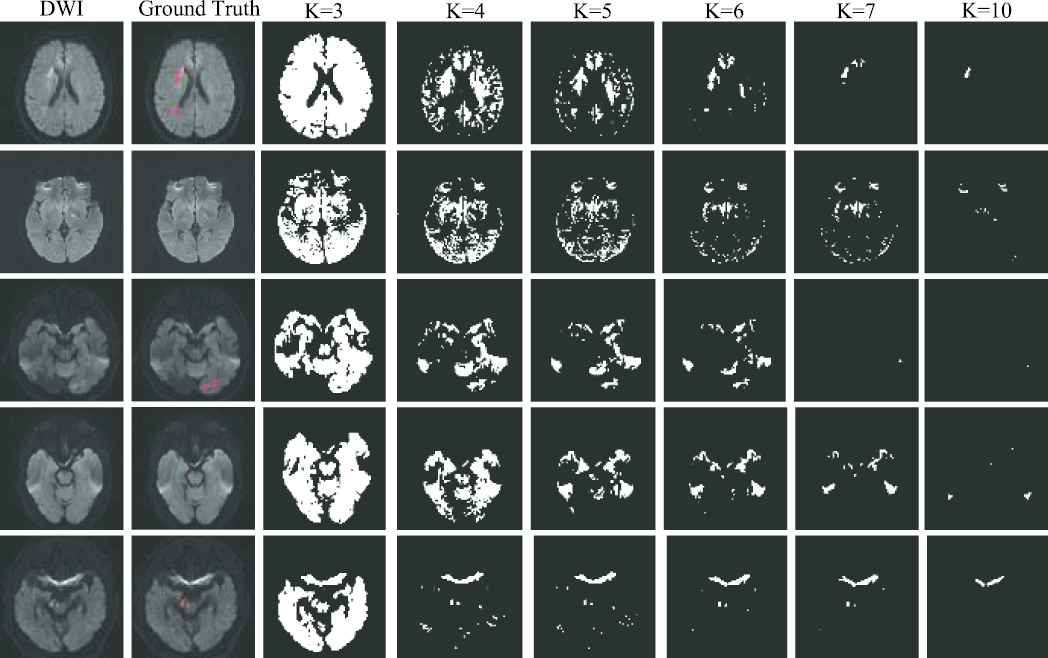

As the AIS lesions appear as hyperintense on the DWI, we adopt K-means clustering algorithm to identify the hyperintensive regions. Note that the artifacts on the DWIs are also the hyperintensive regions, making it crucial to fine-tune the value of K. As we can see from Figure 8, when K=3, the lesion regions and most of the normal regions are divided into a class. When K=4, there is a little improvement, however, artifacts will be in the same cluster as the AIS lesions including the artifacts around the lesions, thus, the clustering lesion regions will be larger than the true lesions. As the K increases, the clustering lesion regions will gradually decrease from greater than the true lesion regions to the near true lesion. The first row and the third row in Figure 8 show that some clustering lesion regions have disappeared when K=7, and more clustering lesion regions will disappear when K=10.

Figure 8

Examples of clustering map. The first two columns show the original diffusion-weighted image (DWI) and the ground truth, respectively. The last six columns show the clustering maps with the clustering number of 3, 4, 5, 6, 7 and 10, respectively. The ground truth is depicted on the DWI, and highlighted in red. Best viewed in color.

In our work, we propose to use a small amount of fully-labeled subjects to search the optimal parameters in a grid search manner, and use DC as the metric. The results with K=3,4,5,6,7,10 are summarized in Table 3. As we can see from Table 3, the best threshold δ decreases as K when K=3,4,5,6 and the performance is improved. However, after K=7, the performance begins to decline.